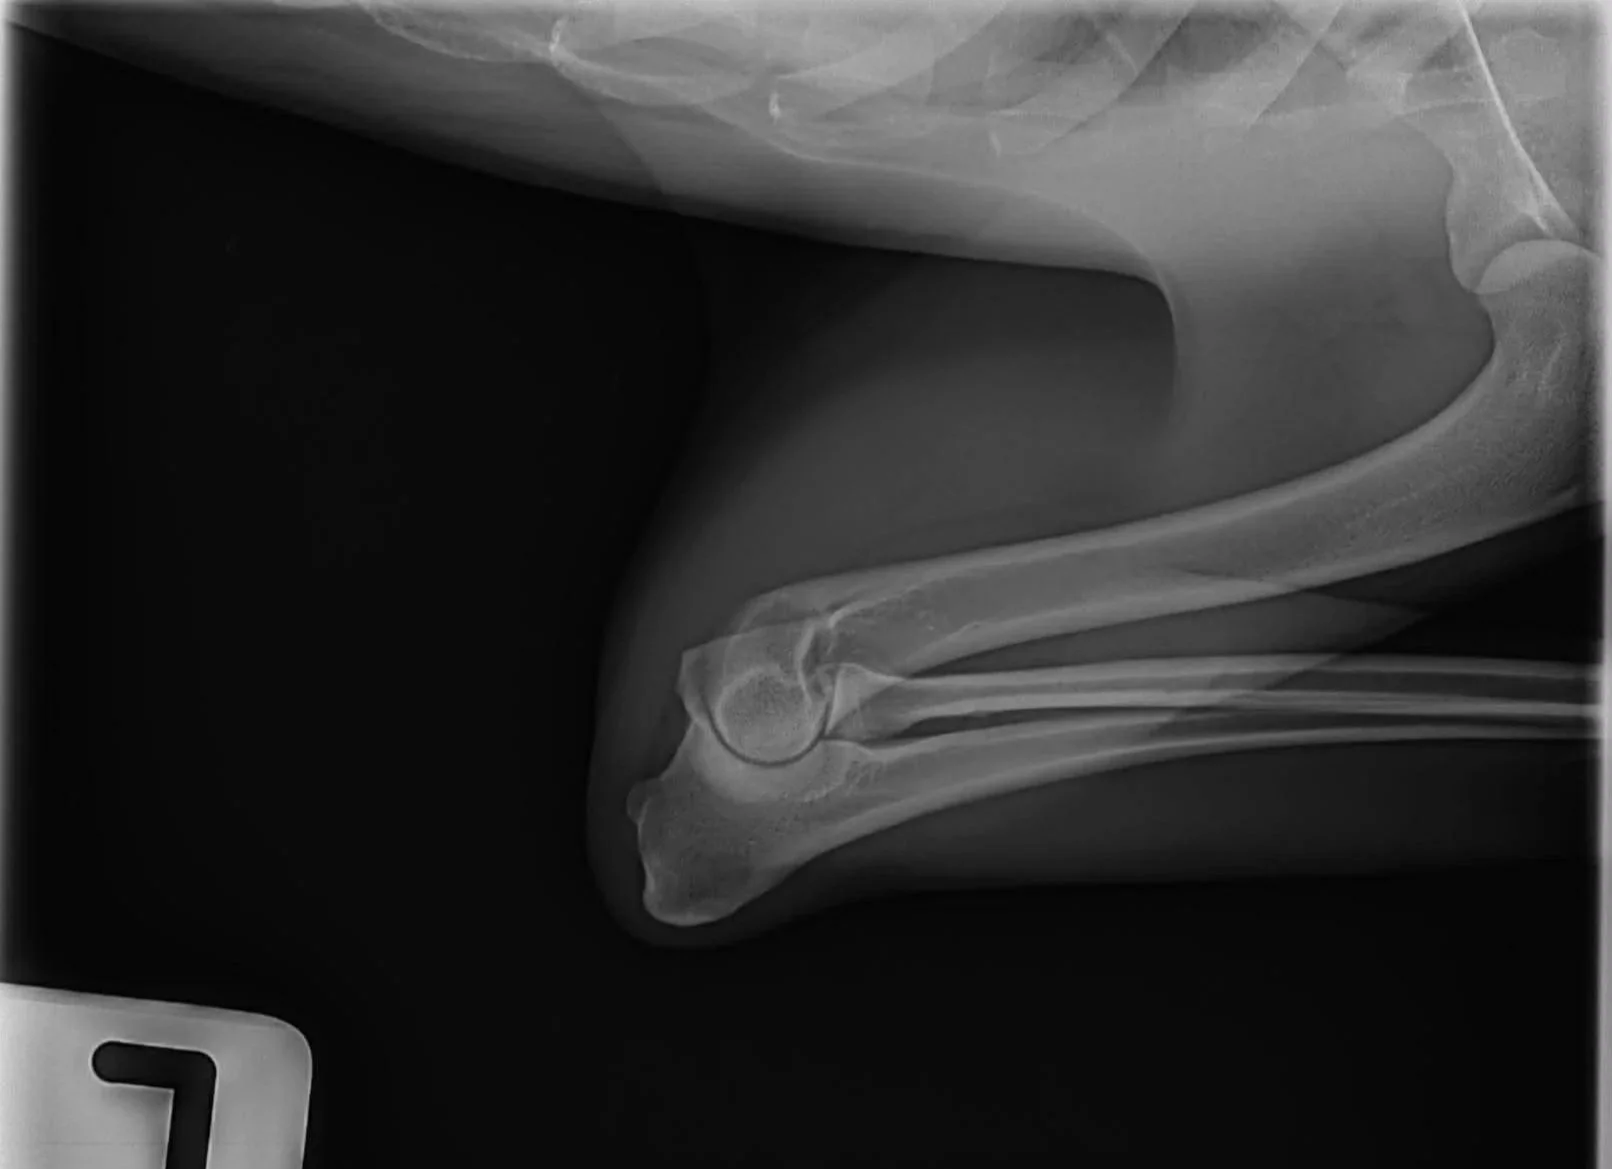

Elbow Dysplasia

Summary: Elbow dysplasia is recognized by an abnormal conformation of the elbow joint, leading to a painful grinding of bone-on-bone between the ball and the socket of the joint. Arthritis, mobility issues, and swelling at the elbow are common symptoms seen in dogs with this condition.  In affected individuals, both surgery or supportive care may be viable options, as recommended by your veterinarian.

Screening: Available in the US through the OFA database which will evaluate each elbow individually through radiographs taken by your vet and assign a grade to each elbow. Elbows may be unaffected (“normal”), unilaterally affected, or bilaterally affected. Elbows can be evaluated at two years of age or older.